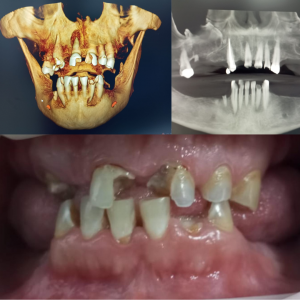

Caso Real: Rehabilitación Total con Prótesis de Carga Inmediata Superior e Inferior

Presentamos un caso de éxito en el que un paciente recibió una rehabilitación completa con prótesis de carga inmediata tanto en la arcada superior como en la inferior.

Antes del Tratamiento

El paciente presentaba pérdida dental severa y deterioro óseo, lo que afectaba su capacidad para masticar y su confianza al sonreír.